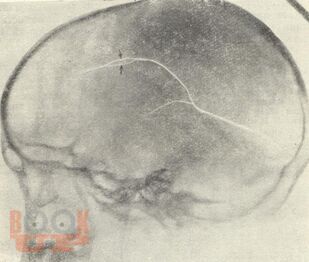

В представленном учебном пособии в виде краткого реферата описаны классификация черепно-мозговых травм, симптомы сотрясения, ушиба, сдавления головного мозга. Отдельный раздел посвящен родовой черепно-мозговой травме у детей. Большое внимание уделено бытовой травме, раздельно описаны открытая и закрытая травмы черепа, их особенности у детей. Имеются иллюстрации в виде рентгенограмм с признаками травм. Весьма ценными являются вопросы для самоконтроля и тестовые задания. В указателе литературы даны основные источники, обращает внимание разработки самих авторов в виде специальных монографий по этой тематике.